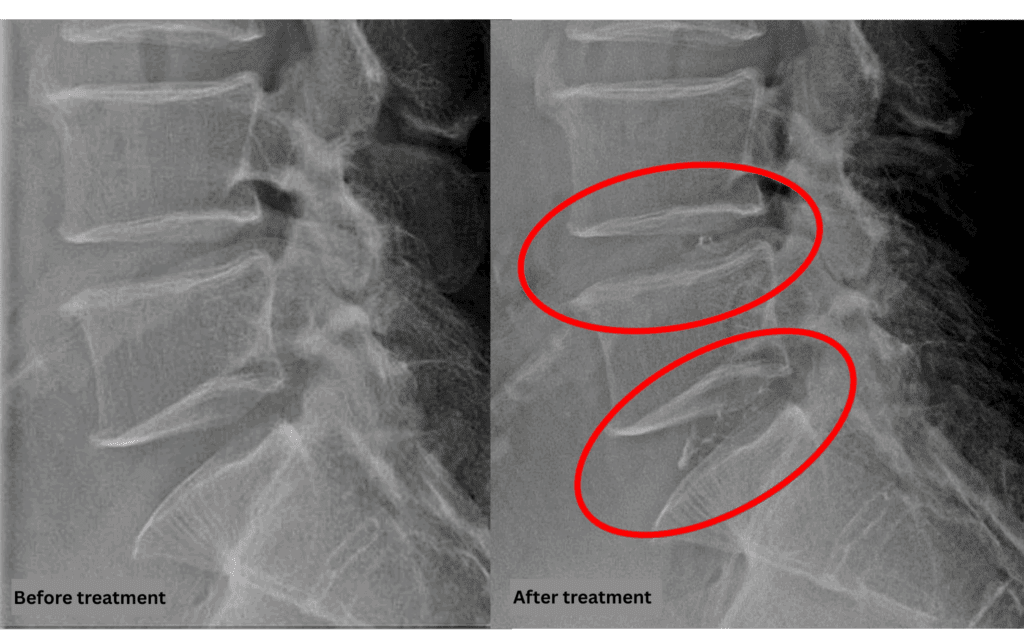

After consulting with the patient, the Cellgel Method was performed on L4/5 and 5/s.

The treatment was performed by our administrative director, Dr. Kotera.

The treatment took about 30 minutes.

After resting in the recovery room, the patient was able to walk home unaided.